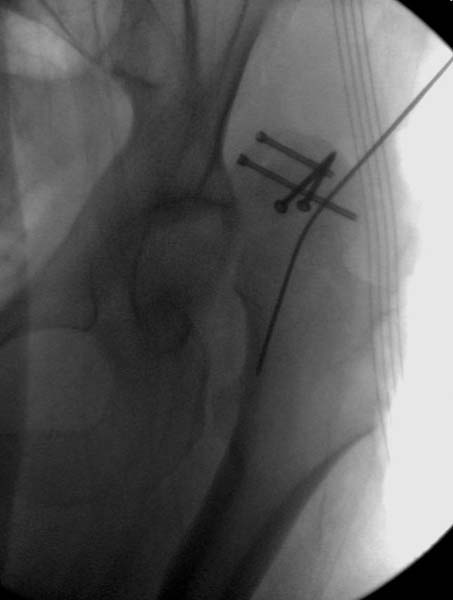

Около 11.00 вечера больная переведена в реанимацию, без сознания, но стабильная.. На третьий день провели стабилизацию перелома бедра антеградным остеосинтезом.

Закрытый БИОС решает множественные проблемы связанные с лечением переломов, но проблема дистальной блокировки без рентгена до сих пор остается нерешенной. Рекламированные производителями приспособления для дистальной блокировки из-за различной кривизны кости не эффективны или стоит очень дорого (Smith&Nephew SureLock). Задержка операции из-за блокировки не всегда удовлетворяет, и многих вынуждает искать альтернативные методы фиксации. С результатами таких действий, остеомиелитом и несращениями, встречаемся в ежедневной жизни..

Для решения проблемы дистальной блокировки компания DigiMed недавно предложила систему блокировки без рентгена. Пока в стране только два набора и только для антеградных гвоздей, но компания работает над созданием устроиства для других гвоздей тоже..

Результат первых случаев показала отсутствие разницы между занятиями на муляжах, а также Workshop и с удивительной точностью вывел латерально над кожей специальное сверло. Дальше по сверлу тонкий направитель и проводится сверление каннюлированным сверлом....